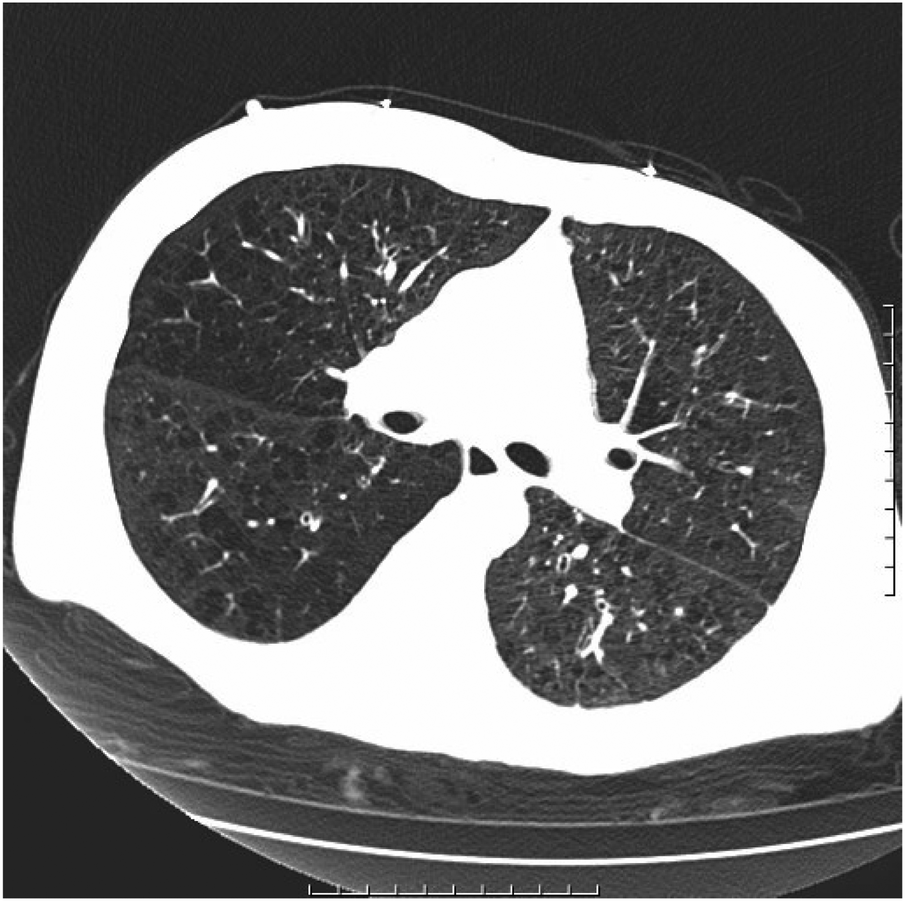

After being admitted to the ICU, the patient quickly developed purpura on both lower limbs, causing the whole body feeling cold and clammy. At this time, the patient's vital signs were as follows: temperature of 36 degrees Celsius, heart rate of 152 beats per minute, blood pressure of 75/46 mmHg, respiratory rate of 35 breaths per minute, and oxygen saturation of 96%. We immediately administered epinephrine to maintain blood pressure, along with milrinone for cardiac support, and used a ventilator to assist the patient's breathing. Bedside echocardiography indicated the patient's left ventricular ejection fraction (EF) was 30%–40%, with segmental dysfunction of the left ventricle and a rounded apex, suggesting the possibility of stress-induced cardiomyopathy (Figure 1B). Chest CT indicated bronchospasm without clear signs of infection (Figure 3). Emergency blood tests showed high-sensitivity troponin I at 3.24 ng/ml and BNP at 4850.2 pg/ml. The electrocardiogram showed extreme clockwise rotation, left atrial abnormality, abnormal Q waves in leads I and aVL, poor progression of R waves from leads V1 to V6, ST segment elevation of 0.05–0.15 mV in leads V3–V6, and T-wave changes (Figure 4). After a consultation with the cardiology team, emergency percutaneous coronary intervention (PCI) was recommended.

Figure 3

Chronic bronchitis and emphysema with multiple bulla formation; both lungs scattered in fibrous foci.

Upon admission to the ICU, the patient's echocardiogram showed a decreased ejection fraction and a rounded apex, ruling out the possibility of structural heart disease. Elevated levels of cardiac enzymes and BNP and hemodynamic monitoring indicators were observed, consistent with stress-induced cardiomyopathy complicated by severe cardiogenic shock. Additionally, the diagnosis of aortic dissection was ruled out due to the absence of obvious tearing chest pain in the patient and minimal difference in blood pressure in the limbs. Pulmonary embolism was also excluded as the patient's D-dimer levels did not show a significant increase. The chest CT scan did not reveal signs of pulmonary edema, and auscultation of the lungs did not indicate significant crepitations, thereby excluding the possibility of acute heart failure.